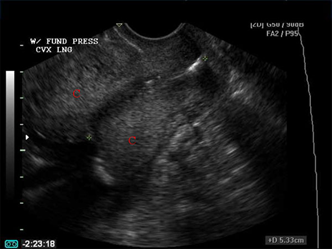

- Nếu cổ tử cung tương đối thẳng: đo straight distance (hình 6.1)

- Nếu kênh CTC cong: đo curve distance hay đo 2 đoạn straight distance rồi cộng lại (hình 6.2, 6.3)

Hình 6.1. CTC thẳng (straight distance)

Hình 6.2. Cổ tử cung không thẳng (curve distance)